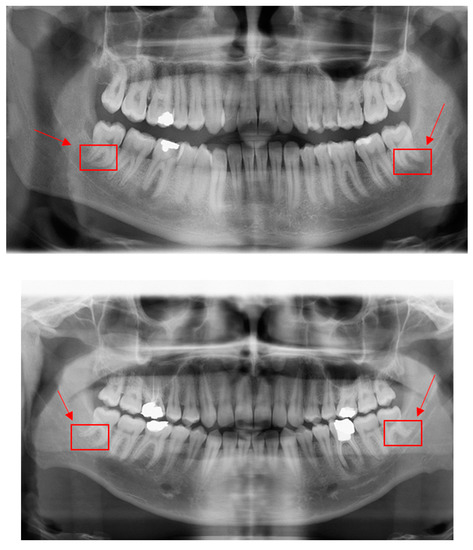

PyTorch and Google CoLab were mainly used to implement deep learning models regarding root dilaceration detection. Figure 2 shows PRs with root dilaceration as an example to show the inputs used for the proposed object detection solution. Before feeding into the deep learning models, data were pre-processed, which included typical operations such as resizing, flipping, normalizing and padding.

Figure 2.

Example PRs with root dilacerations. Red rectangular boxes indicate dilacerated roots that were also used as ground truths. Arrows show dilacerated roots.